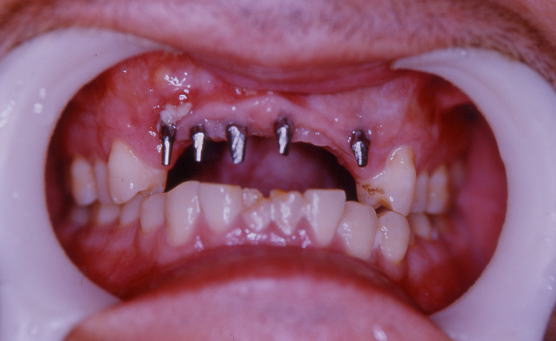

症例101